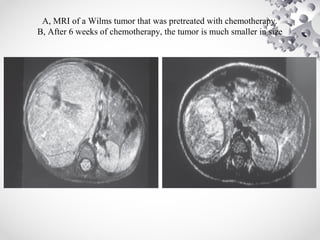

A, MRI of a Wilms tumor that was pretreated with chemotherapy.

B, After 6 weeks of chemotherapy, the tumor is much smaller in size

• Inoperability shouldnot be based on preoperative imaging studies, which can overestimate local tumor extension. • Pretreatment with chemotherapy almost always reduces the bulk of tumor and renders it resectable. • Majority of reduction in tumor volume occurs in first 4 weeks of chemotherapy.

A, MRI ofa Wilms tumor that was pretreated with chemotherapy. B, After 6 weeks of chemotherapy, the tumor is much smaller in size